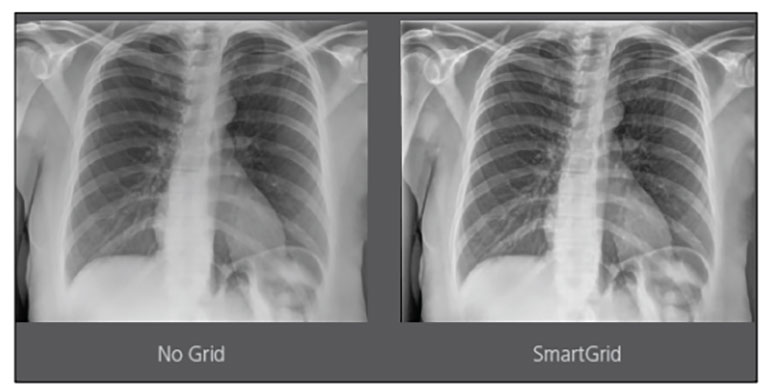

Carestream Introduces New Software Update to Boost Diagnostic Accuracy

Carestream today announced the latest update to its Image Suite V4 Software, MR 11: a series of enhancements to help improve customer confidence and increase diagnostic accuracy [...]

Our Carestream Focus HD 35/43 Retrofit Detectors, powered by Image Suite Software, are an ideal solution to step up to full digital X-ray for customers who simply cannot compromise on image quality. It seamlessly integrates into existing setups, bringing the power of full digital X-ray with minimal disruption and maximum clarity, along with the following benefits: